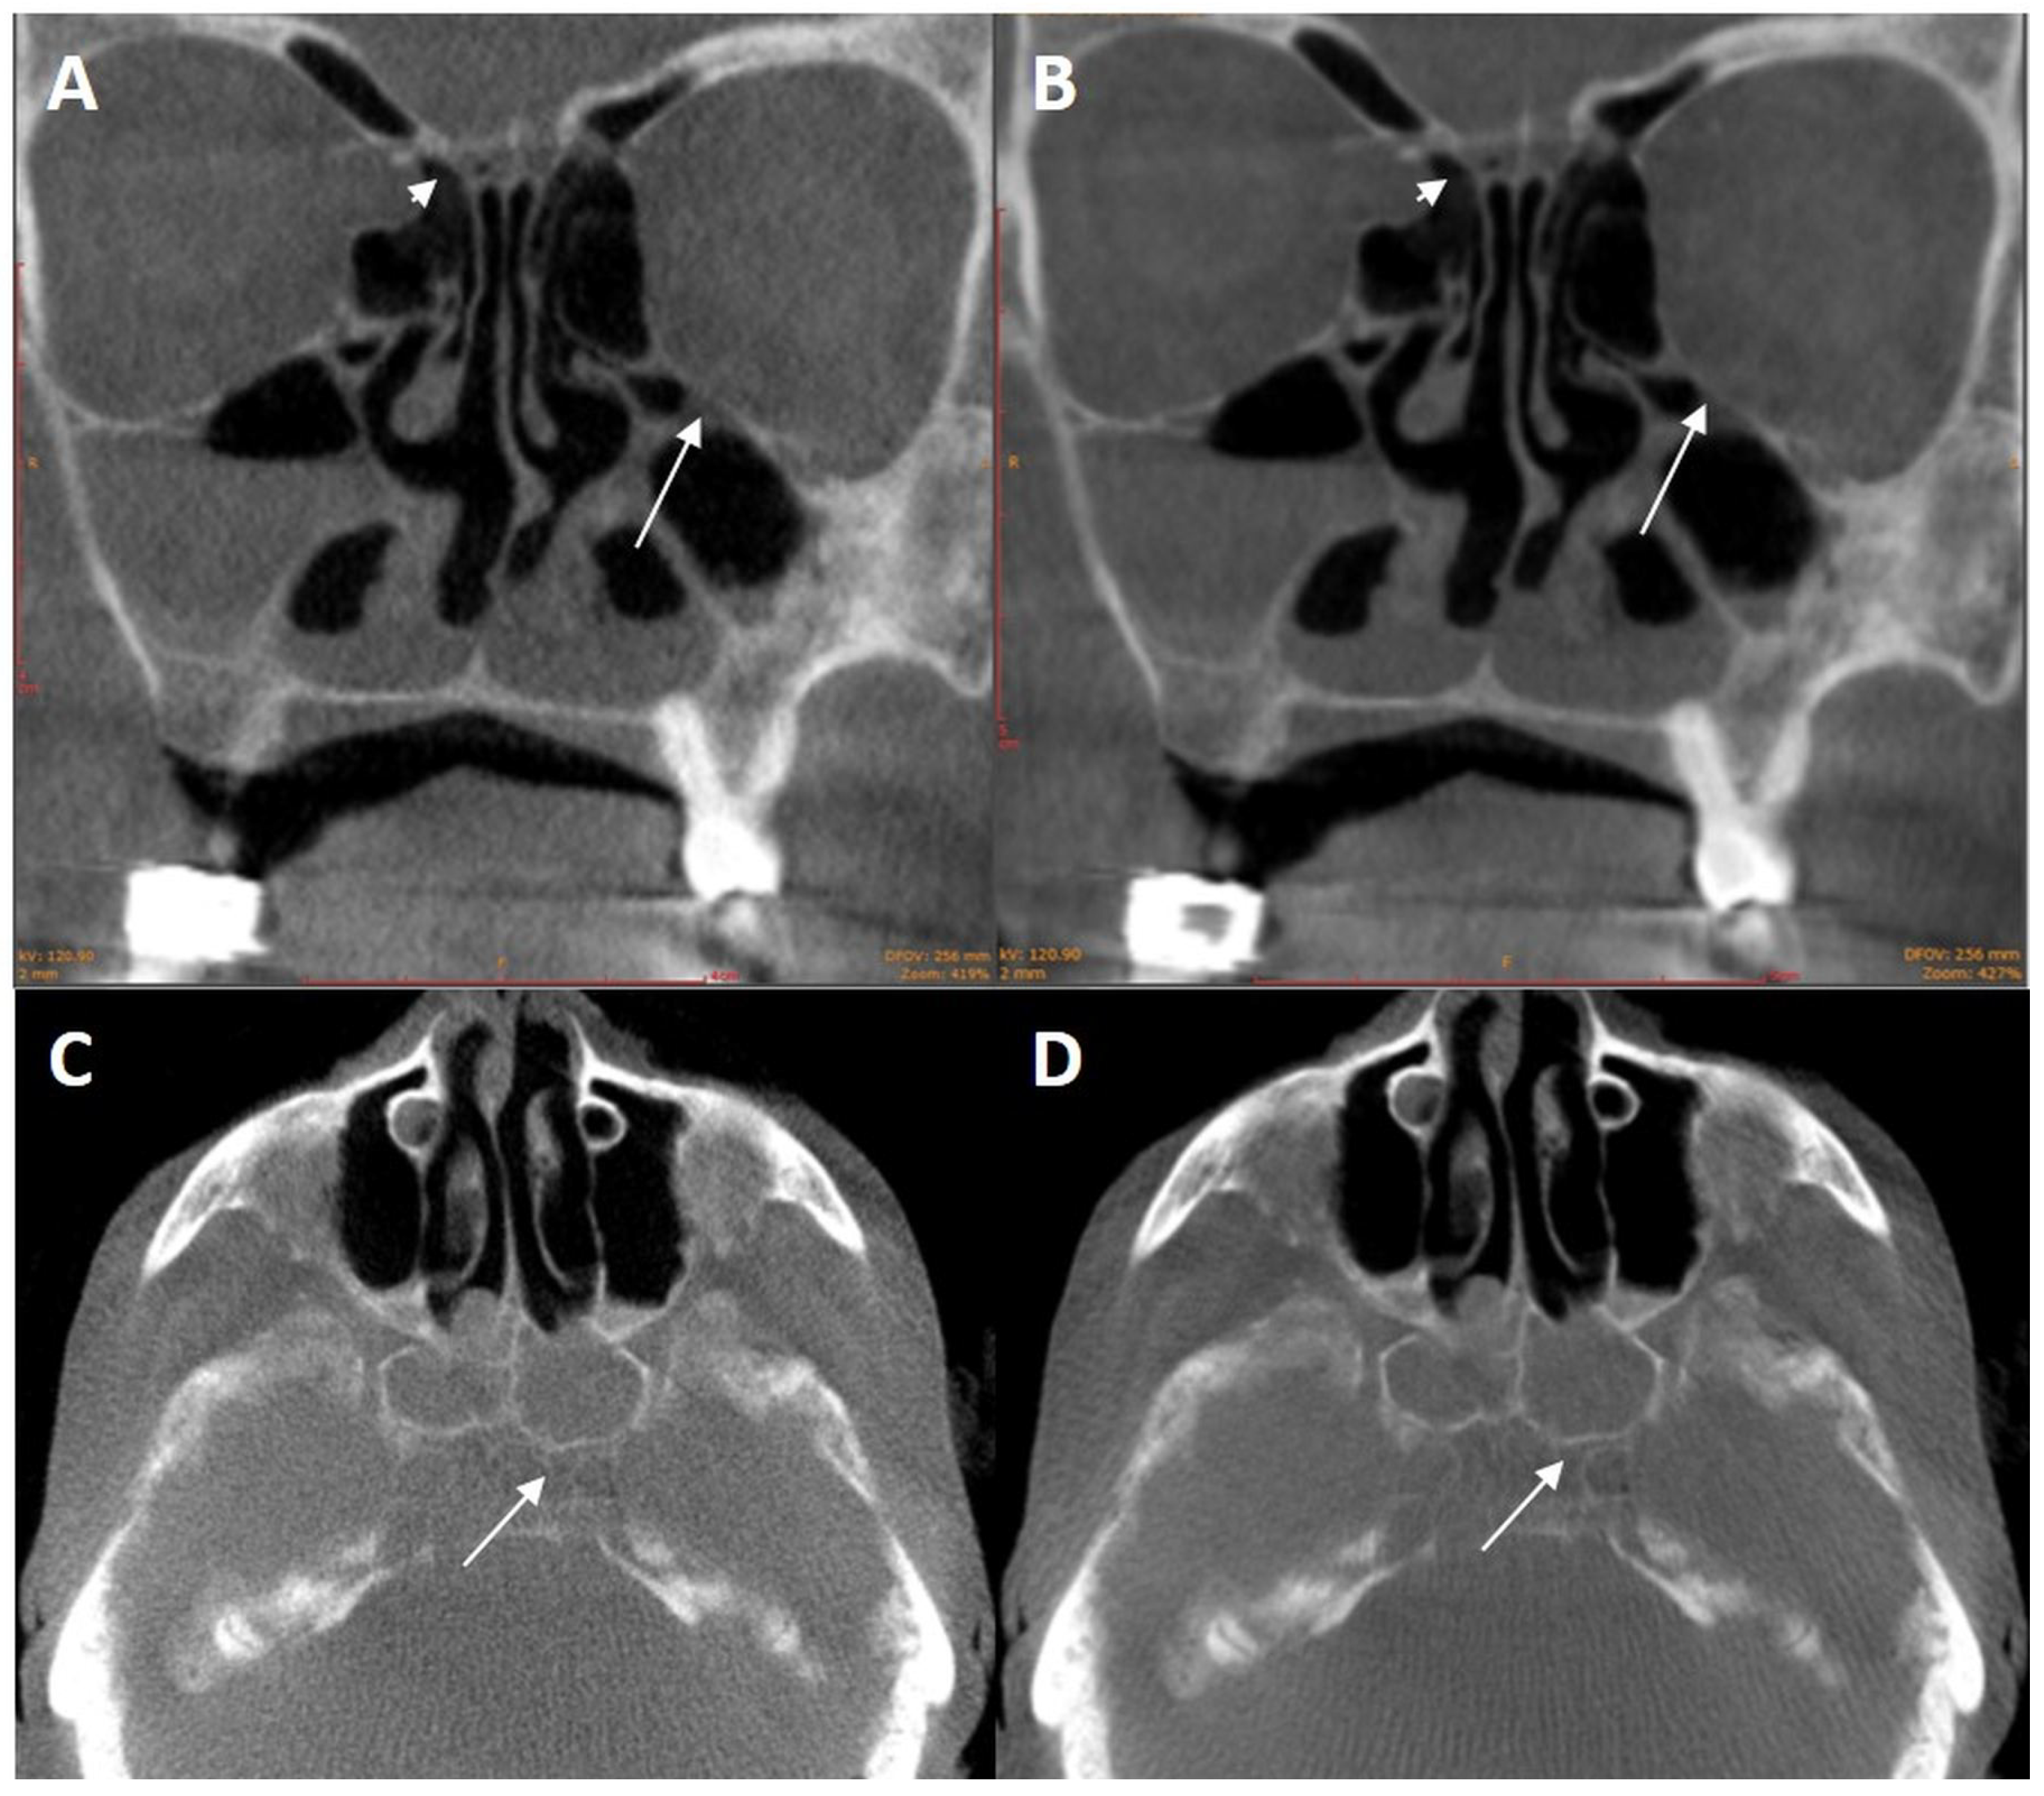

3.1.1. Variation of Tube Voltage

3.1.2. Metal Artifact Reduction Algorithm

3.1.3. Kernels

3.2. Results for Cadaver Heads 2–4

3.2.1. Pre-Filtration with 0.2 vs. 0.3 mm Copper Filter

3.2.2. Pre-Filtration with 0.4 mm Tin Filter